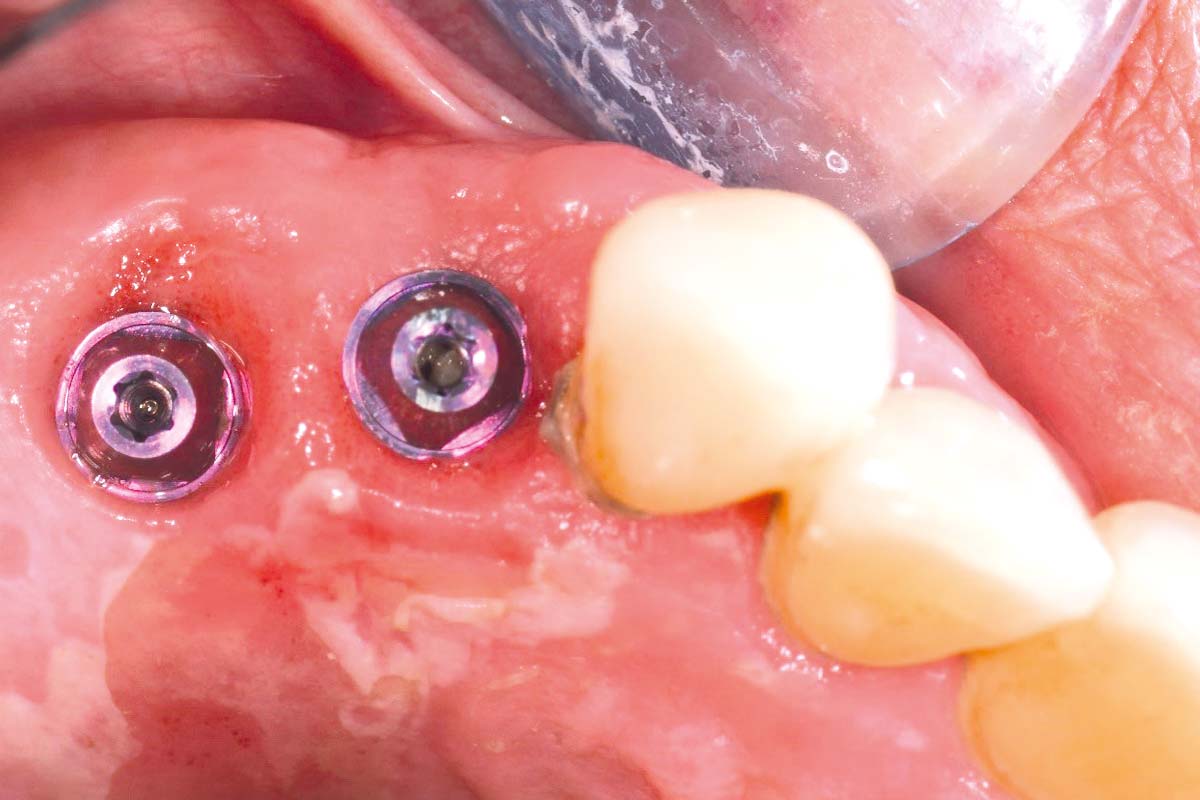

Three months post-augmentation, substantial bone regeneration and soft tissue integration were observed. The final outcome demonstrated improved aesthetics, function, and implant stability. A final CBCT scan confirmed the success of the procedure, showing sufficient bone volume, density, and proper ridge alignment.